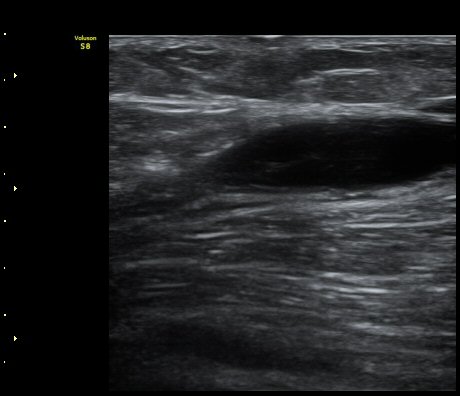

¹«¸ µÚ ¿À±Ý Á¾´Ü¸é°Ë»ç¿¡¼ ³»Ãøºñº¹±Ù°ú ¹Ý¸·¾ç±Ù »çÀÌ¿¡ Àú¿¡ÄÚ ¼ö¾×Àú·ù°¡ °üÂûµÈ´Ù(»çÁø 1).